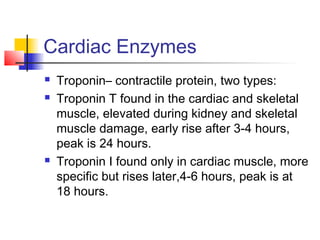

Cardiac enzymes PPT